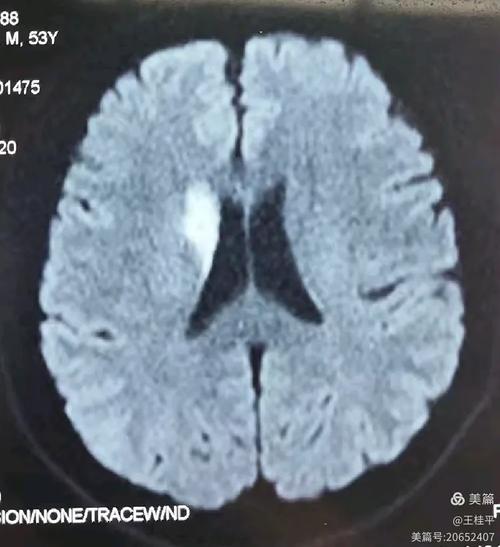

大面积:这是最关键、也是最严重的一点,它意味着堵塞的血管主干非常粗大,导致其供应的整个脑叶(如整个额叶、颞叶、顶叶,或它们的组合)都发生了梗塞,梗死的脑组织范围很广,通常梗塞体积会超过50-80毫升,甚至更多。